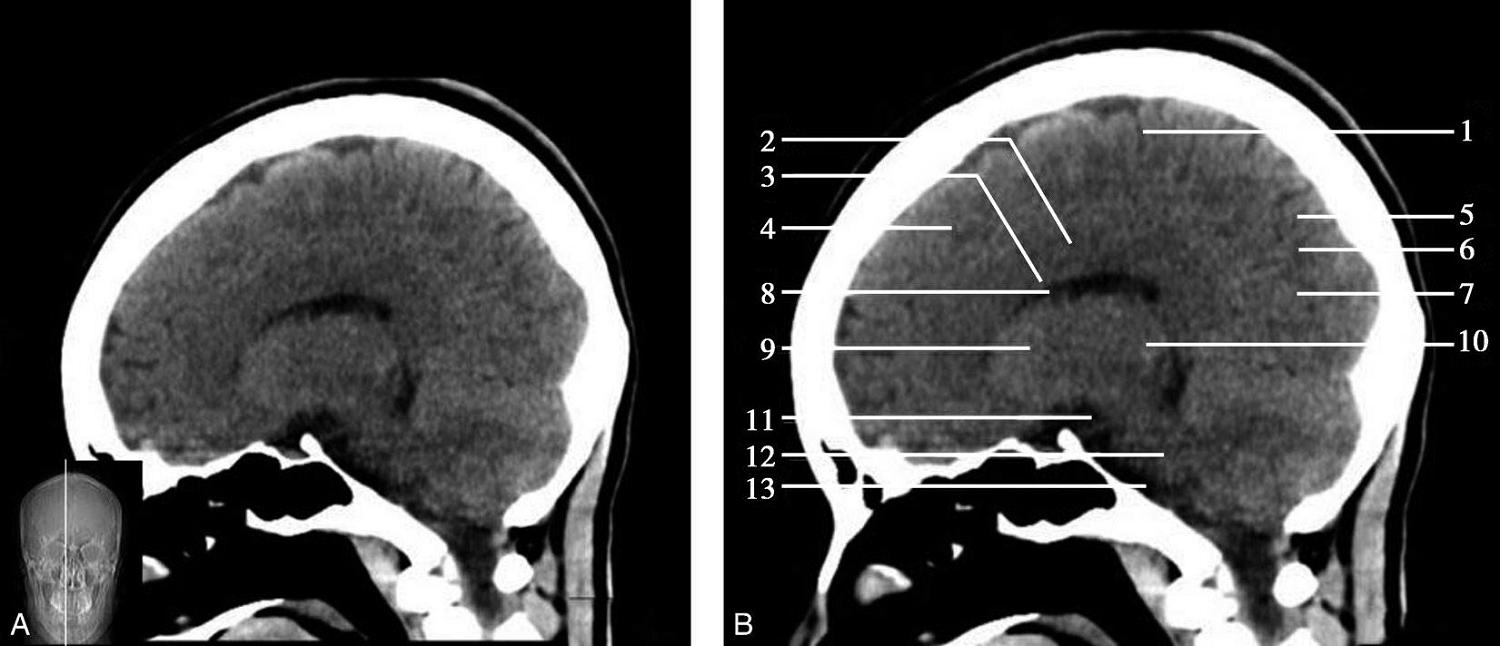

重要结构:胼胝体、垂体、中脑导水管、扣带回、中央沟、第三脑室、斜坡(图1-2-59、图1-2-60)。

图1-2-59 正中矢状面CT

A.矢状面;B.矢状面标注

1.中央沟;2.扣带回;3.胼胝体体部;4.侧脑室;5.中脑;6.胼胝体膝部;7.穹隆;8.第三脑室;9.胼胝体压部;10.垂体;11.中脑导水管;12.第四脑室;13.脑桥;14.蝶窦;15.斜坡;16.小脑扁桃体;17.延髓

此层面可显示胼胝体全貌,它位于层面中央区域,是呈上凸下凹的弧形结构,由前向后分为嘴、膝、体和压四部分。扣带回环绕胼胝体上方,扣带沟位于扣带回的上方。大脑半球中部和后部分别可见较深且恒定的中央沟和顶枕沟。中央沟为是额叶顶叶分界标志。

胼胝体下方为侧脑室及穹窿,第三脑室借穹窿与前上方的侧脑室体部分开,背侧丘脑的内侧面以及中脑顶盖分别为第三脑室的外侧壁和底。第三脑室向前籍室间孔与侧脑室相通,向下经中脑导水管通第四脑室。中脑腔狭窄呈管状,即称为中脑导水管,中脑导水管畸形,常见者为导水管的分叉畸形和狭窄,其次可见中脑导水管膈膜,造成先天性脑积水。

脑干由中脑、脑桥和延髓组成,自第三脑室底向下后稍斜行,移行于颈髓。由上至下,脑干腹侧可见脚间池、桥前池和延髓池,脑干背侧可见大脑大静脉池、四叠体池和小脑延髓池。

垂体位于蝶鞍内,其前部为腺垂体,后上部分为神经垂体。垂体下方为鞍底及蝶窦,上缘因鞍膈存在而平直,垂体借垂体柄向上连于丘脑下部。垂体的前上方见视交叉和视束。斜坡作为前颅窝底的重要组成部分与多个重要结构相比邻,矢状位呈三角形,颅内肿瘤或颅外鼻咽部恶性肿瘤均可侵犯至此,原发肿瘤常见为脊索瘤。小脑幕居枕叶和小脑之间,向后下连接窦汇,向前至中脑后方游离,称小脑幕切迹。小脑幕下方为小脑扁桃体。成年人小脑扁桃体下缘由枕骨大孔向下疝入椎管超过5mm称为Chiari畸形,以矢状位显示最佳。